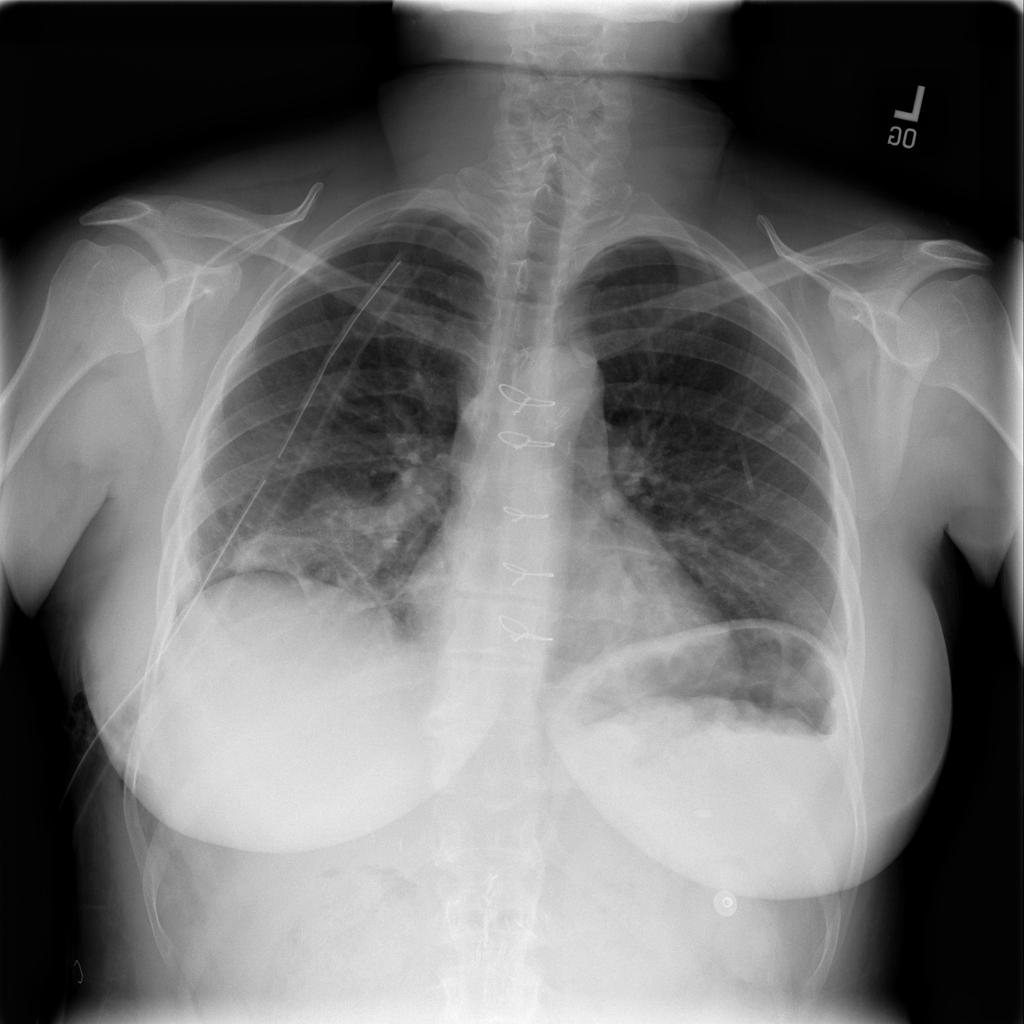

PAT-4639 · IMG-013Pneumothorax

PAT-4639 · IMG-013

AP